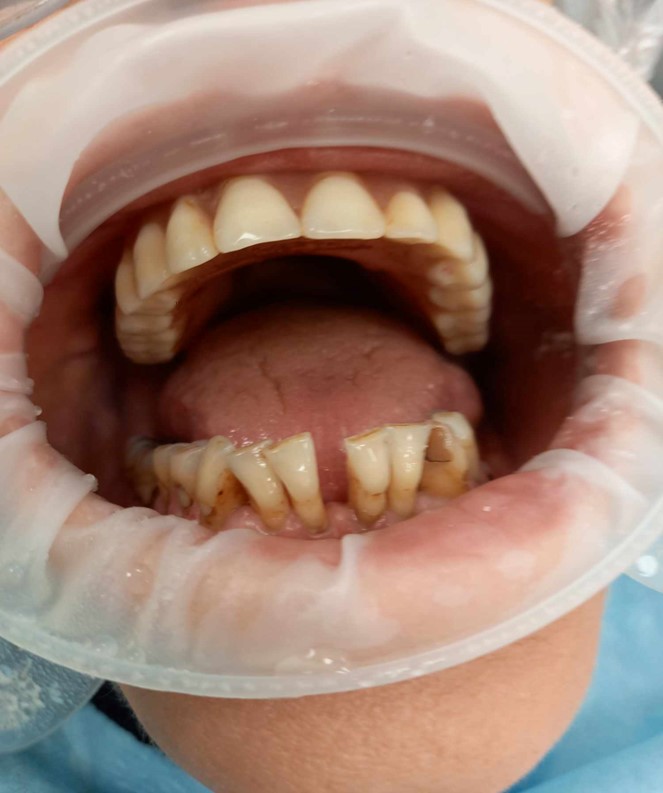

Do mojego gabinetu zgłosił się pacjent, lat 51, zaniepokojony zwiększoną ruchomością dolnych zębów siecznych (ryc. 1). Kilka miesięcy wcześniej stomatolog poinformował pacjenta, iż ruchomość jest związana z chorobą przyzębia i zastosował unieruchomienie zębów drucianą ligaturą. Jednakże szyna nie była stabilna, utrudniała pacjentowi mówienie oraz drażniła język i błonę śluzową dolnej wargi, dodatkowo pacjent nie zaakceptował szyny ze względów estetycznych. Ostatecznie szyna została usunięta. Czy są inne możliwości unieruchomienia zębów u pacjenta?

Ryc. 1. Zdjęcie uzębienia pacjenta z ruchomością zębów siecznych żuchwy.